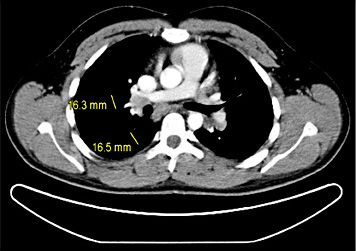

1st patient: this 43-year-old man presented with left-sided testicular discomfort. Contrast-enhanced scrotal ultrasonography demonstrated unspecific irregularities of the intratesticular echo pattern (Fig. 1). Scrotal MRI was likewise inconclusive. The classical serum tumour markers were all in the normal range. Therefore, the patient was put on a surveillance schedule. As the patient moved to another city, he was lost to follow-up. But, enquiries disclosed that orchiectomy for classical seminoma (pT1, clinical stage [CS] 1) was performed on him at another institution 4 months after our primary assessment. The serum level of miR371a-3p at the time of primary examination was RQ = 39.45 which is much higher than the normal range. Knowledge about the elevated miR-level would clearly have changed decision-making. No follow-up measurements of miR371a-p were available.